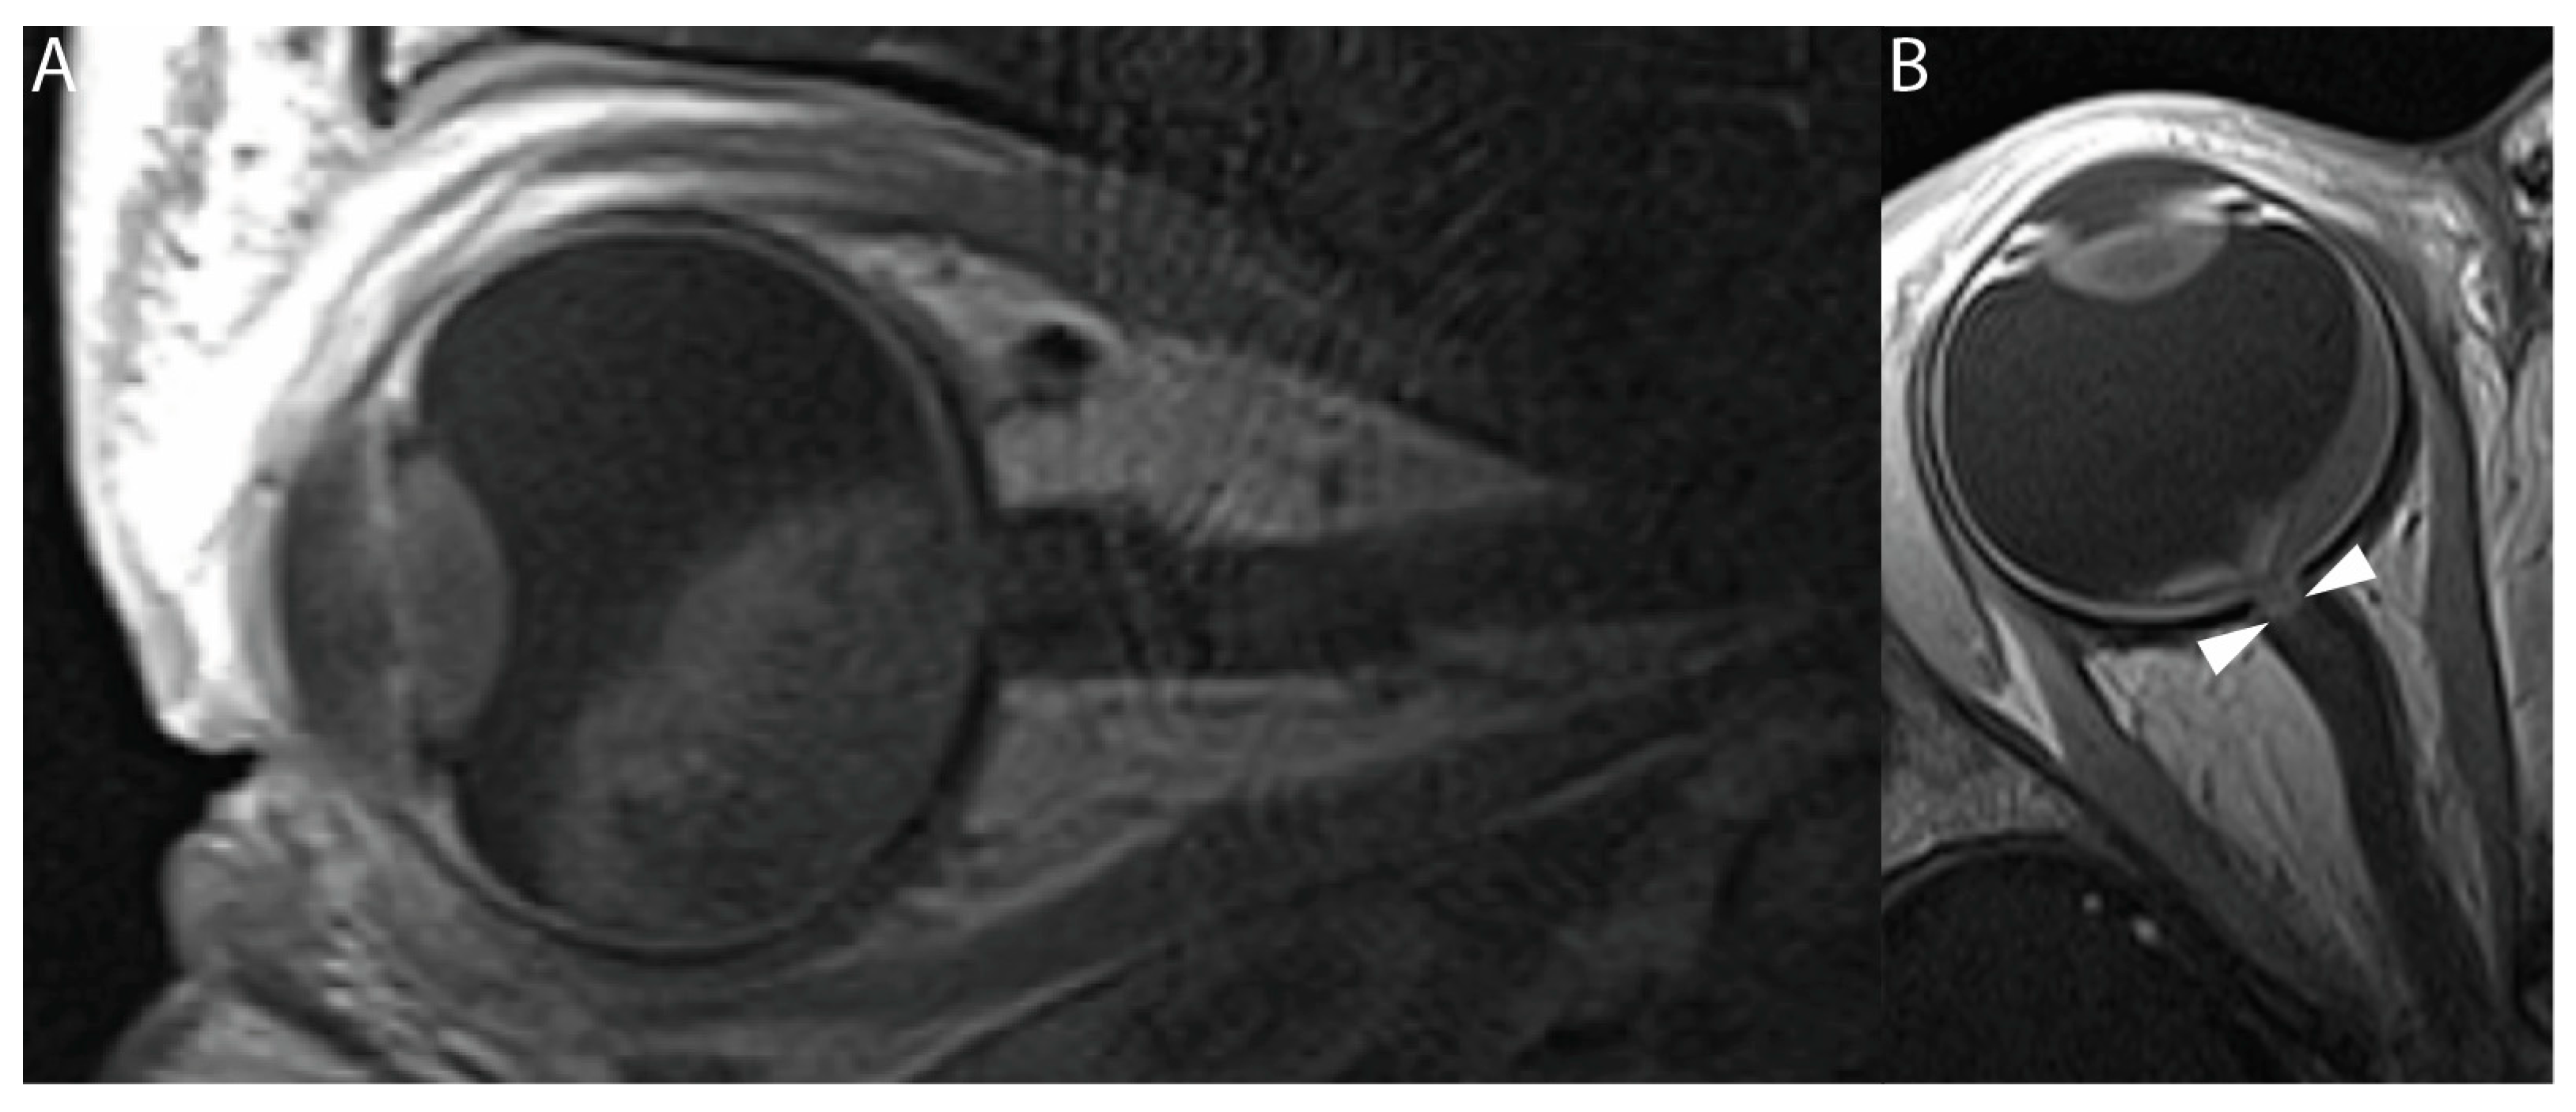

3.2. Qualitative Imaging Features